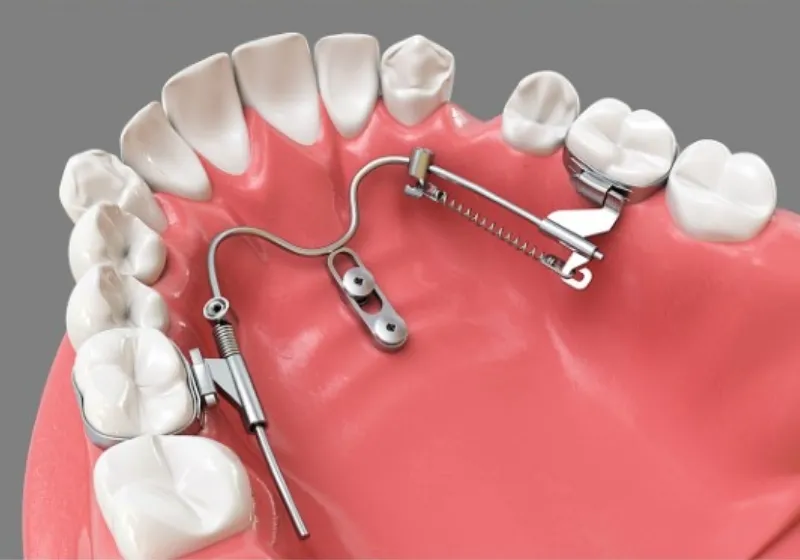

SHU-lider® EX(拡大)

上顎急速拡大と大臼歯遠心移動が同時に可能

SHU-lider® RE(後方)

ダイナミックな歯体移動によるPhysiologicdrift効果を活用

SHU-lider®+ 舌側ブラケット装置

口蓋部後方の最大固定源を利用した大臼歯遠心移動と前歯エンマス・リトラクション(後方移動)

・矯正用アンカースクリューとデジタル技術を応用した、スライディング・メカニクス(歯につけられたブラケットスロットのなかのワイヤーを滑らすように歯を移動させていく仕組み)による3Dメタルプリント矯正装置です。